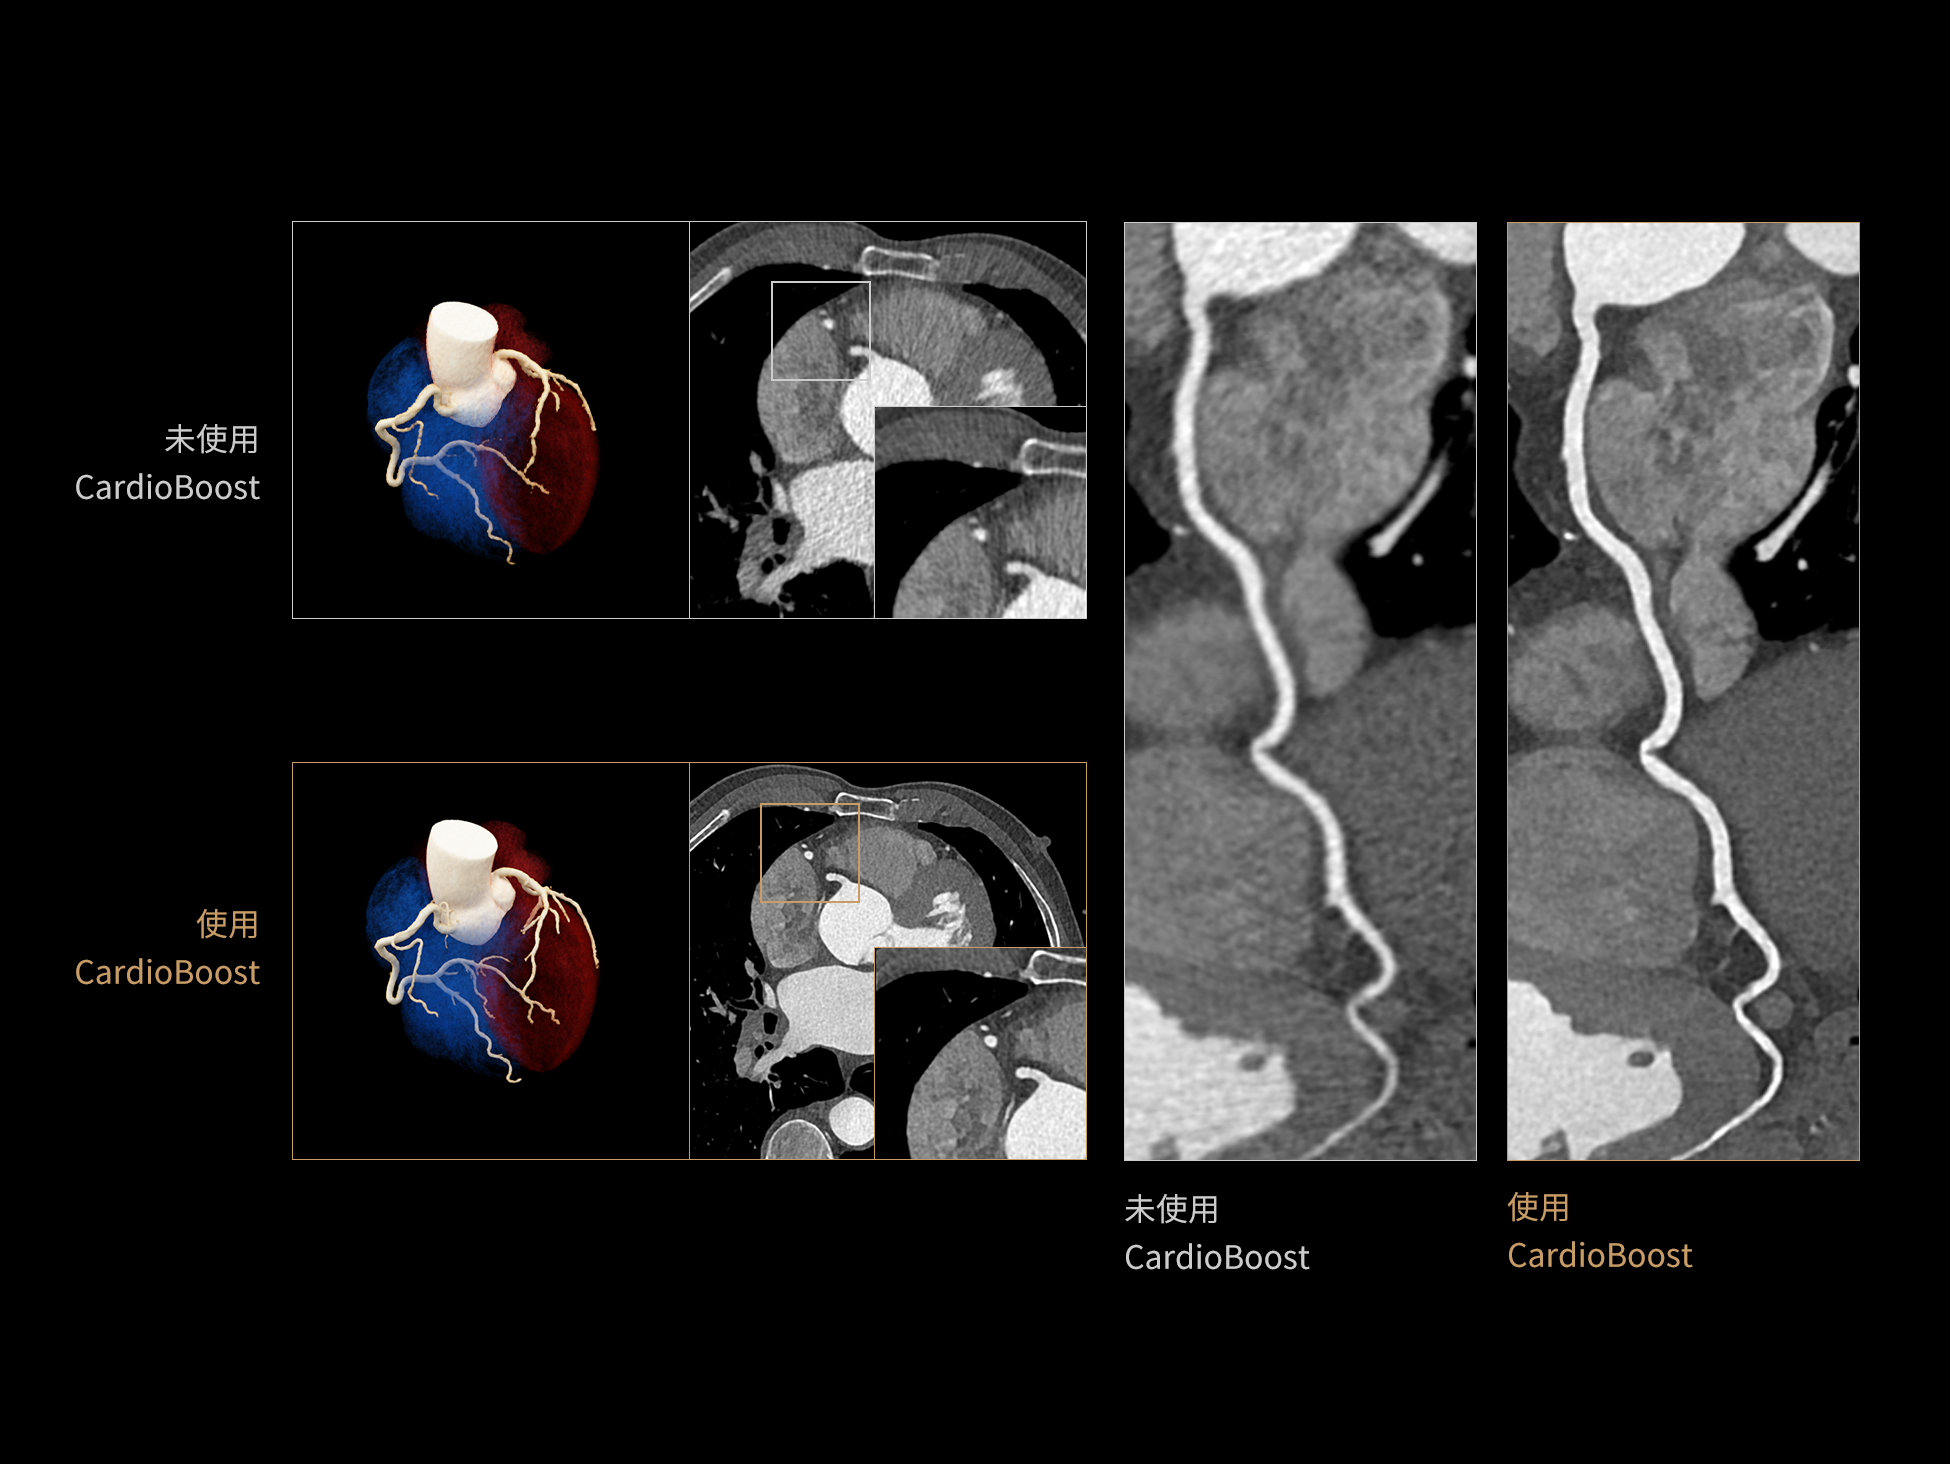

CardioBoost:专属网络设计,重塑心脏影像表现

目前心脏的 CT 检查还存在辐射剂量偏高、空间分辨率不足、 致密钙化伪影影响冠脉狭窄程度评估等方面的限 制[1][2]。CardioBoost 技术专为心脏 CT 高清成像而开发,通过 3D 神经网络的深度学习技术,利用先进的注意力机制在识别关键成像特征方面的出色表现,能够精确地聚焦于斑块、支架以及微小血管等关键细节,清晰展示这些结构与冠脉血管的边界,从而显著提高诊断的准确性,并提升医生的诊断信心。创新的 CardioBoost 心脏图像重建算法,不仅实现了图像清晰度的提升和伪影的去除,更能在减少辐射剂量的同时,保证心脏图像的高质量和图像纹理的自然。

CardioBoost核心创新

采用 3D 神经网络的空间结构优势与精细的组织分类能力,CardioBoost 技术优化了组织对比,高清展示血管斑块,使斑块与血管边缘的轮廓清晰可辨,提升斑块诊断与评估的精确性。

借助 3D 神经网络设计、空间注意力机制聚焦与特征强化作用,CardioBoost技术提升图像的空间分辨率,实现冠脉支架的高清成像,对支架形态与管腔通畅度的评估更精准。

CardioBoost 整合先进的 3D 神经网络和空间注意力机制,大幅增强数据处理的速度与精确度。该技术能有效抑制由致密钙化引起的晕状伪影,清晰展现钙化斑块的原始结构和大小,对冠脉狭窄的评估更加精确可靠。

对比度强化模块

分辨率强化模块

伪影抑制模块

超真实渲染(Hyper Realistic Rendering,HRR)可将医学影像数据转化为高度真实、细节丰富的三维数字可视图像。相比传统VR渲染,HRR在解剖结构与图像细节的还原上更为精准,助力临床直观地理解病灶特征与组织关系,更加适用于术前规划、教学演示及患者沟通。

HRR超真实物理渲染:精准还原解剖细节的三维可视化技术